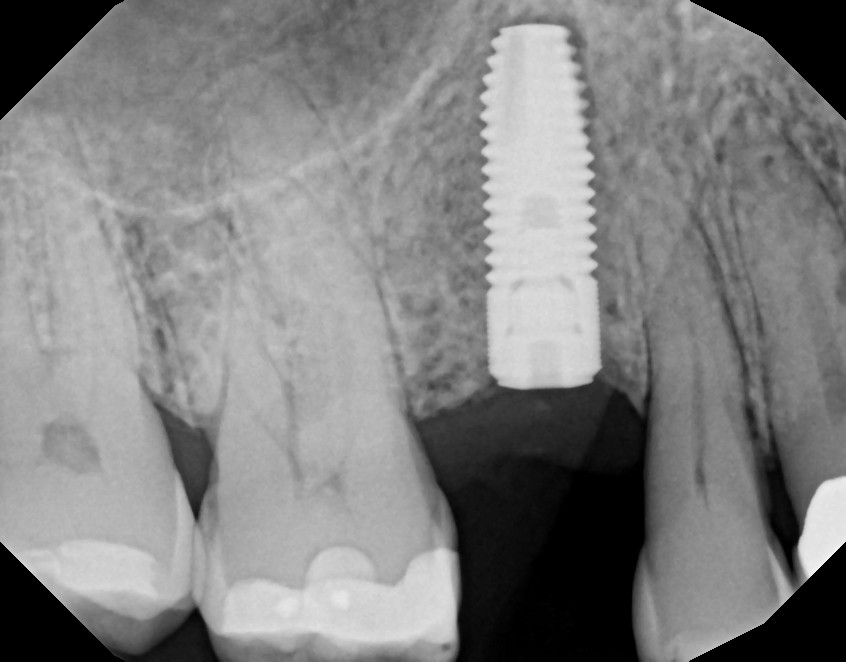

- Cover a dental implant

If we find that the tooth is too severely damaged, we may need to remove it. We will do everything we can to save a tooth, but in some cases, the damage is beyond repair. We can discuss restoration options after the extraction, which may also involve a cap. Implants, for example, are topped with a crown.

- X-rays

- A cone-beam CT scan